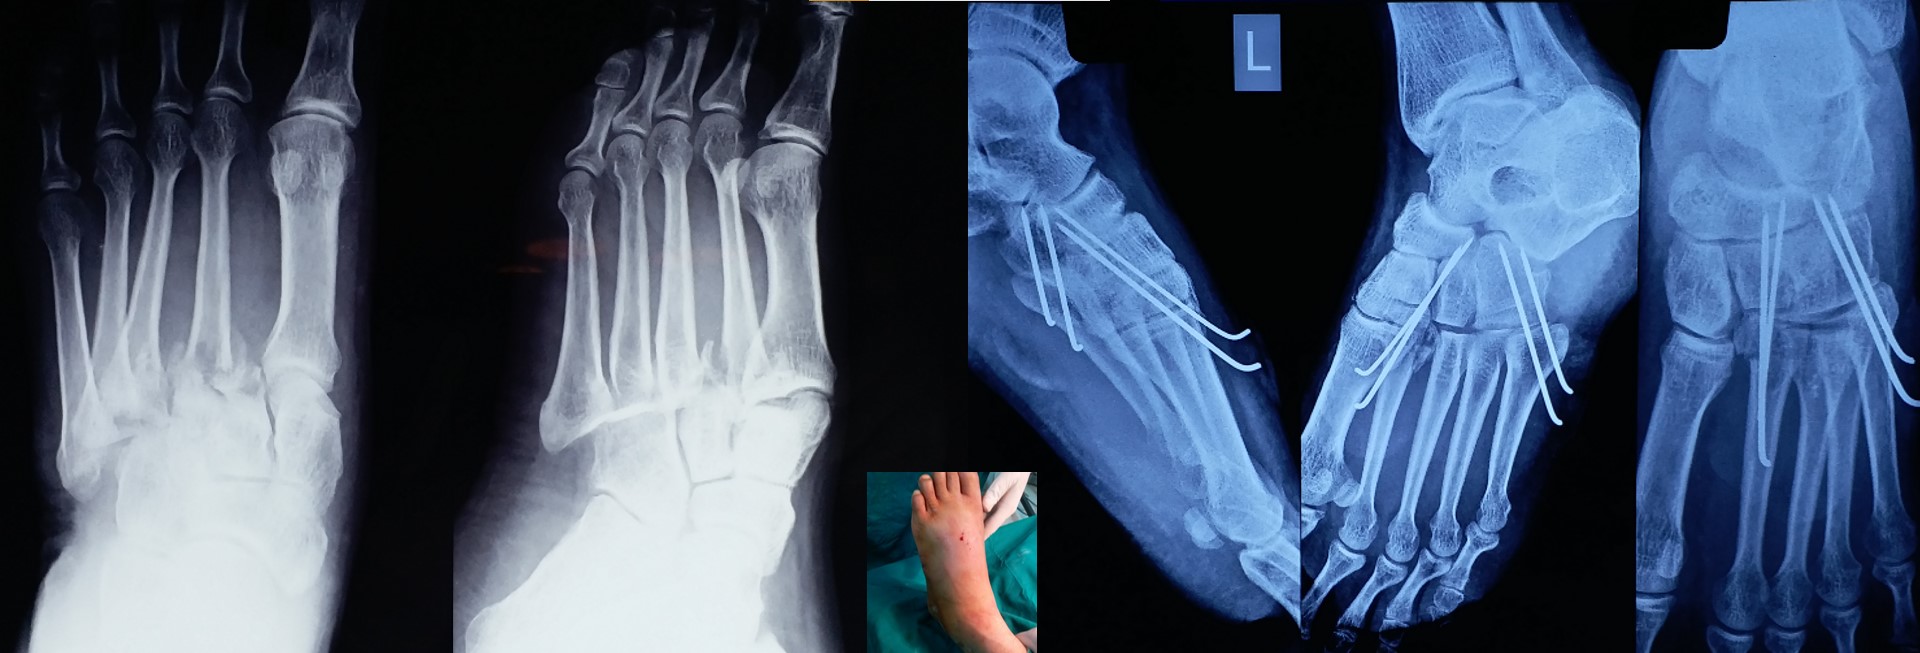

CRPP ( Closed Reduction Percutaneous Pinning )

• Most of the metaphyseal fractures of both upper and lower limbs can be successfully treated by CRPP.

• It can be applied to any intraarticular fractures, distal end radius, elbow, ankle and foot.

• It can be applied to diaphyseal region adjacent to metaphysis in pediatric fractures, especially distal 3rd arm, forearm and leg fractures.